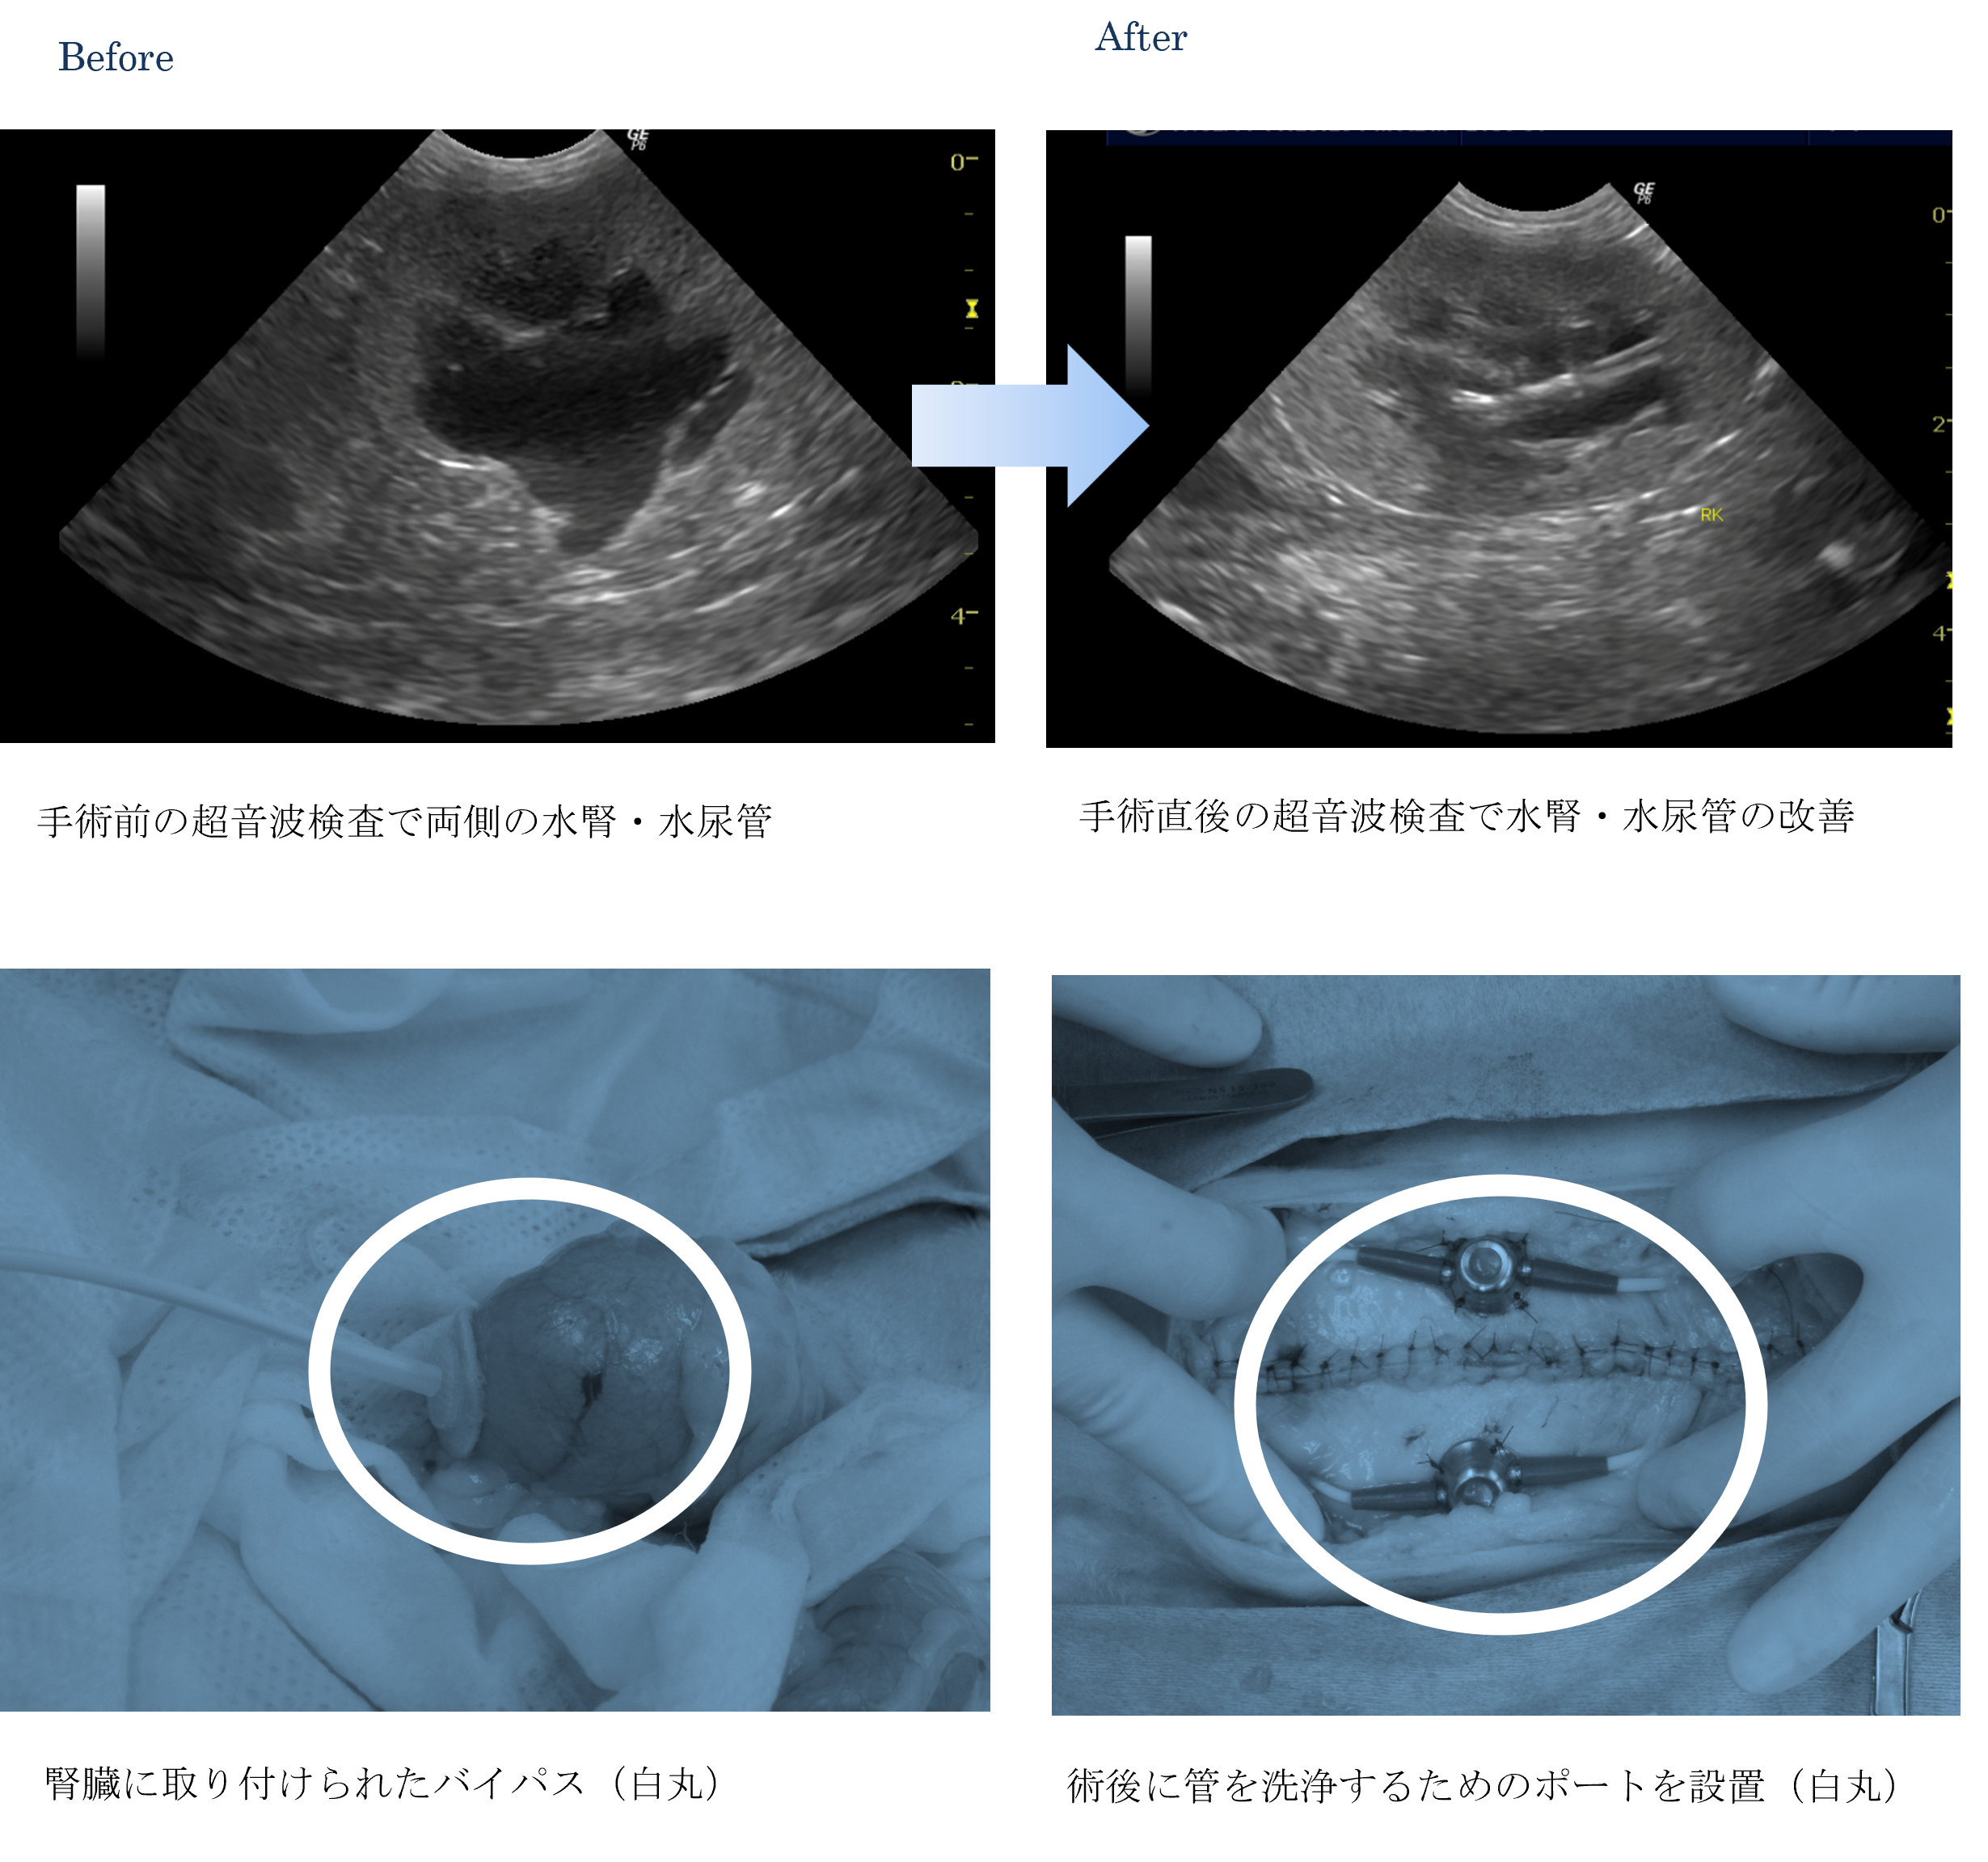

各種検査より、両側の尿管閉塞による急性腎不全(水腎症)と診断しました。

ご家族と相談した結果、両側の腎臓膀胱バイパス(SUBシステム)手術をすることになりました。

手術前は血液検査でBUN 140以上、CRE 5.4だった数値もすぐに正常値まで下がってくれました。